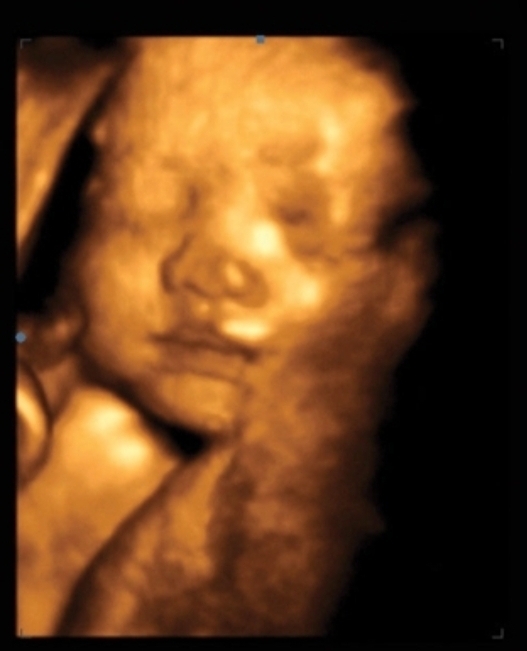

Срок_33недель 3 дня./по узи/,34/3 по месячним.

Сегодня были на узи вес было 2711.